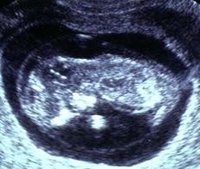

Embarazo

Entre las técnicas ecográficas existentes, hay una que ofrece mucha información sobre algunas de las posibles anomalías cromosómicas del feto, se trata de la translucencia nucal. Esta técnica es similar a una ecografía normal, pero...